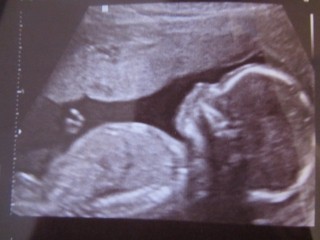

二人目で男の子です。海外在住でエコー検査は2回だけなのでとても待ち遠しかったです。胎動がなく不安でしたが、赤ちゃんはとても活発で動き回っていて安心しました。私の場合、胎盤がお腹側にあるらしく胎動が感じにくかったみたいです。

今回は心拍確認以来の旦那が同行した検診でした。

赤ちゃんはパパの声が聞こえたからか、動きまくっていました。

遂に今回性別が判明して、大望の男の子で二人で拍手して喜びました!

写真の下部に大股開きの中央についてます(笑)